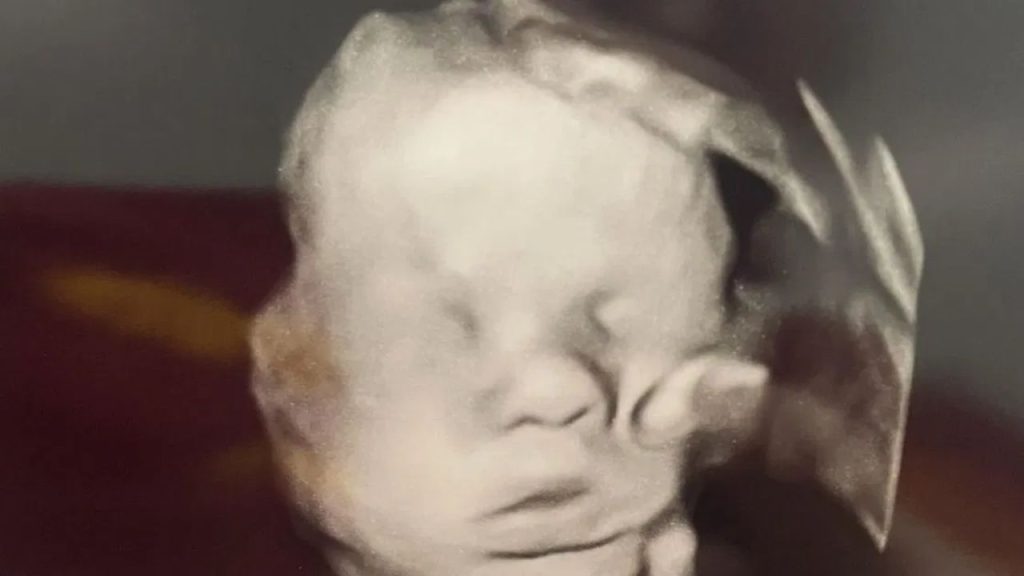

“Isso me assustou no começo, eu não sabia se era normal", confessou a mulher, que teve de ser tranquilizada pelo médico